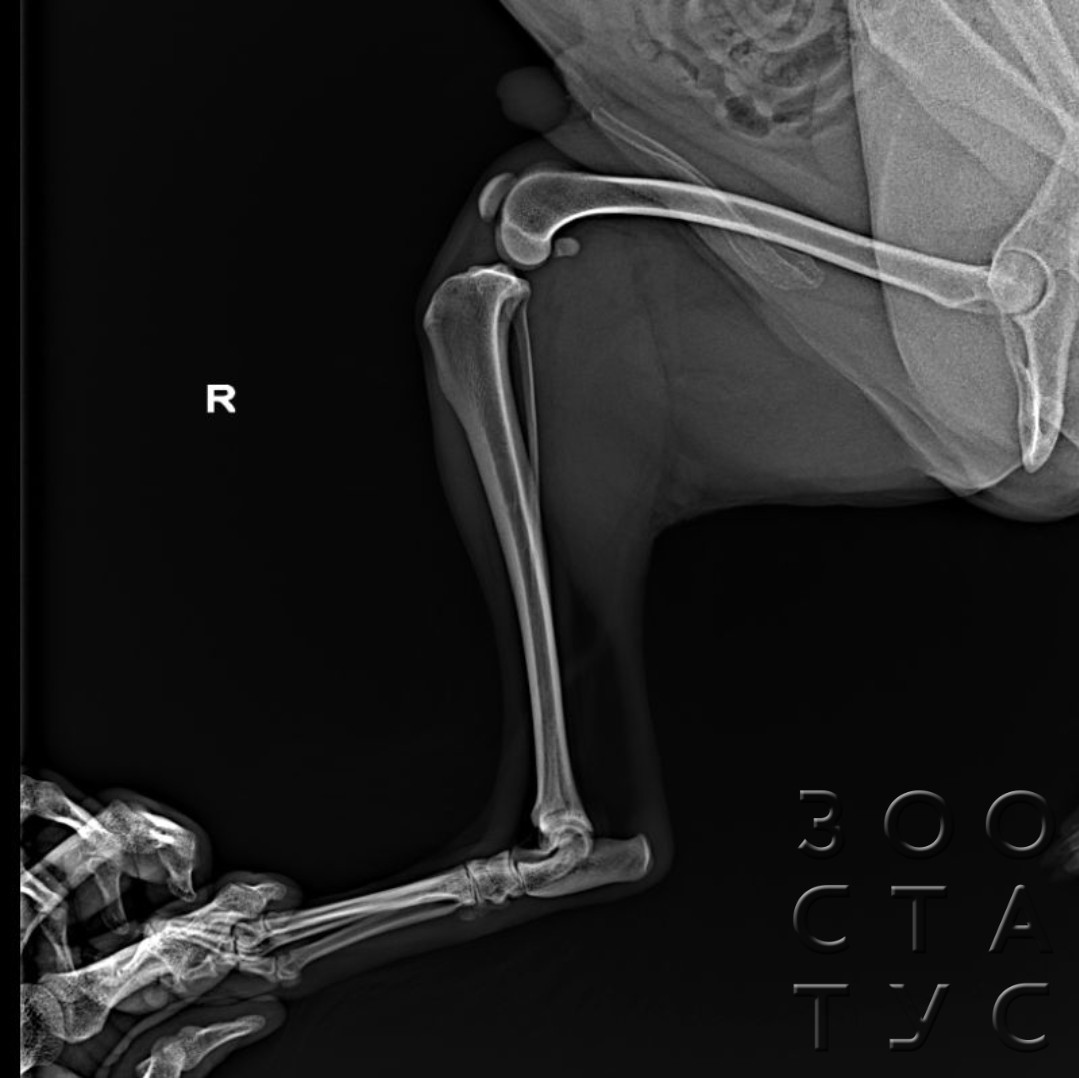

Рентгеновские снимки головы кошки в боковой проекции